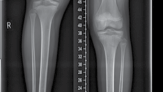

| 43. Monolateral rail (Figure 15.7) 1. If no risk of joint subluxation | |||

| 2. Three half-pins proximal and, at least, three distal to corticotomy | |||

| 44. Circular frame | |||

| 1. If risk of joint subluxation | |||

| 2. Span knee/pelvis | |||

| 3. Arches/two-thirds rings to allow mobility | |||

| 4. Same principles as earlier | |||

| Figure 15.7 Radiograph of femoral limb reconstruction system (LRS) rail. | |||